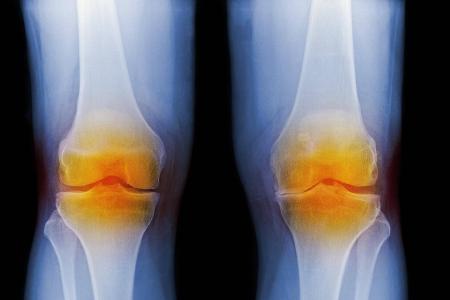

Übergewicht oder Fettleibigkeit strengen die Gelenke an, weil sie übermäßig viel Gewicht bewegen müssen. Ebenso wie Fehlstellungen von Gliedmaßen führen sie zu einer vorzeitigen Abnutzung der Gelenke, was in schmerzhaftem Verschleiß (Arthrose) enden kann.